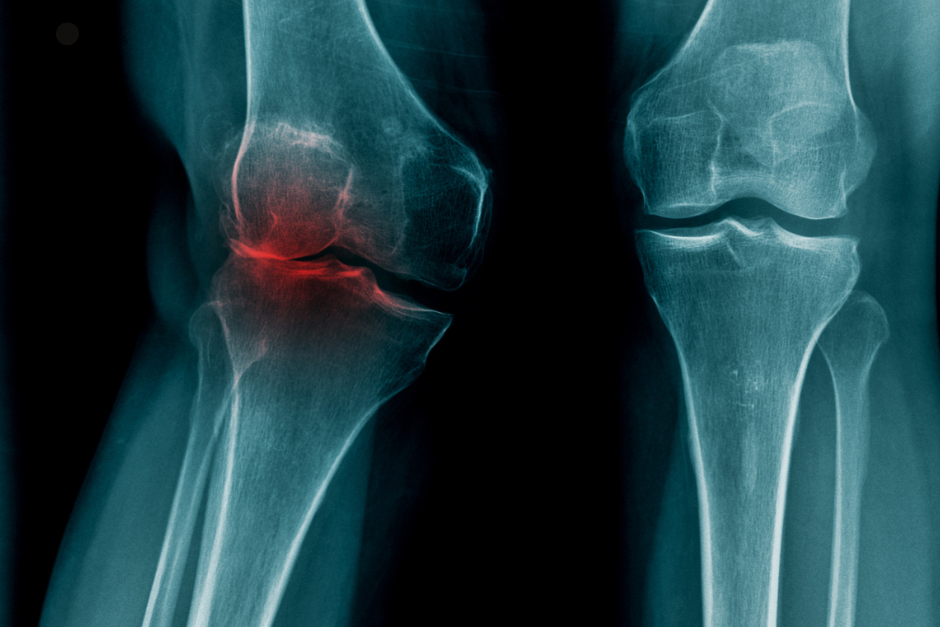

Вальгус колена - это деформация нижних конечностей. Они характеризуются тем, что не образуют прямую линию друг с другом, вместо этого они изогнуты в форме буквы X. Таким образом, колени направлены внутрь, а область под ними - наружу. Кроме того, когда колени сжаты, расстояние между лодыжками превышает 4 или 5 см. Для определения дефекта измеряется отклонение от оси в градусах. Если она составляет менее 10 градусов, то это называется физиологической деформацией осанки, которая не требует лечения. Если же она превышает 10 градусов, то это считается медицинским состоянием, при котором необходимо проконсультироваться с врачом.